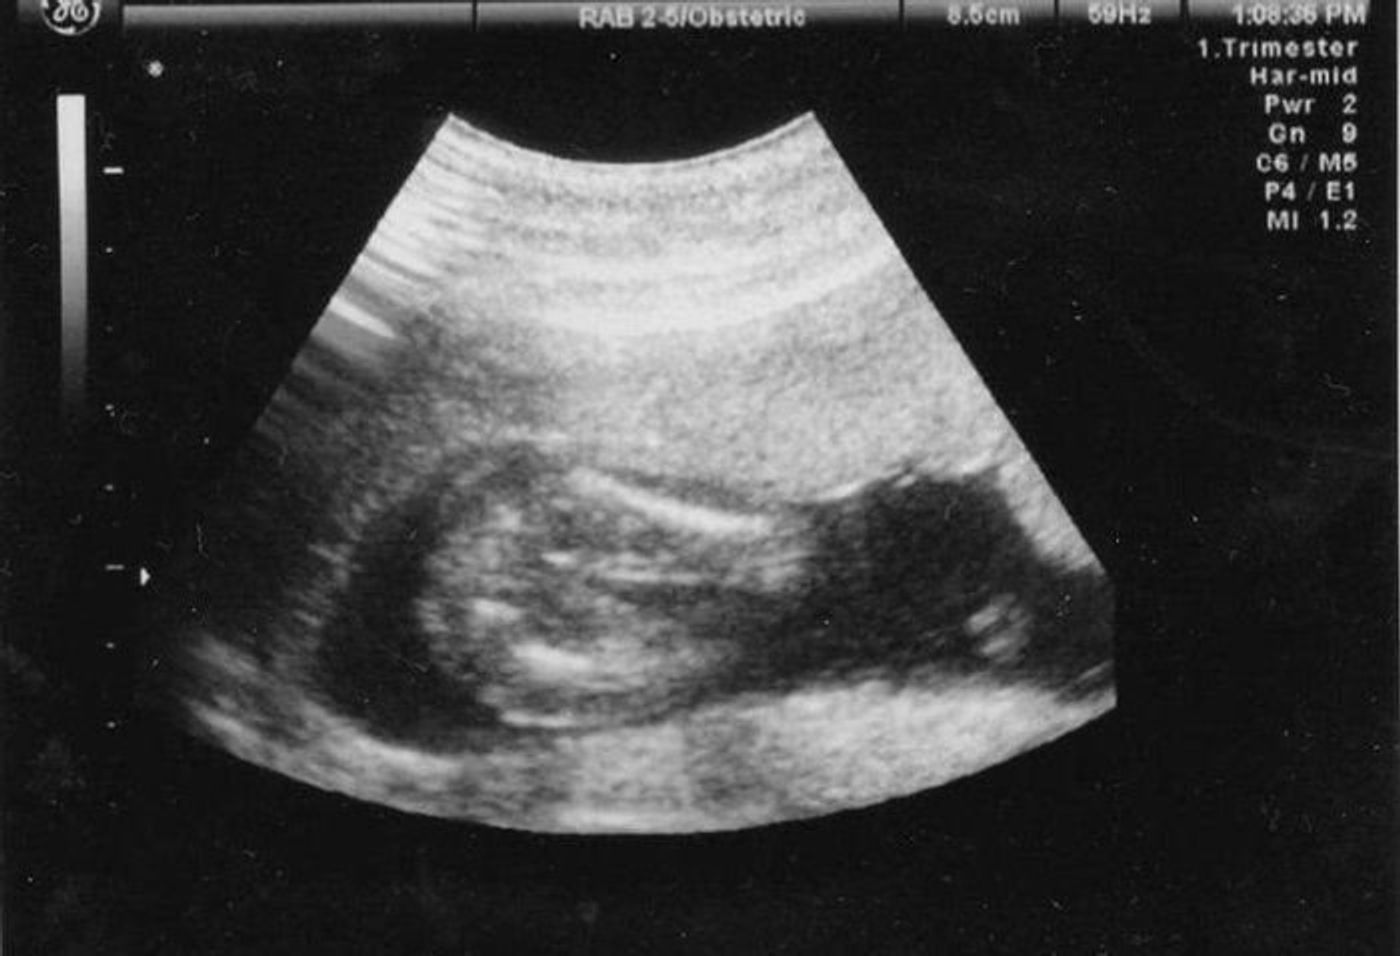

18 週 エコー 女の子- 18 週 エコー 女の子 突起 物 こんばんは 現在妻が妊娠18週なのですが 前回の検診で性別がまだ判断 妊娠 教えて Goo エコーでの性別判断 女の子でしょうか Okwave妊娠週 18w0d BPD (頭の幅) 453ミリ AC (腹部周囲長) 1292ミリ FL (大腿骨長) 251ミリ 体重は225グラム、頭からお尻まで13センチで足を伸ばせばセンチ弱とのこと。 順調だそうです♪ 『ぜひとも性別をお願いします! 』で、エコー開始数秒で写真の通り男の子と

妊娠5ヶ月 妊娠16週 17週 18週 19週 妊娠中期 の超音波写真 妊娠 出産 育児に関する総合情報サイト ベビカム

妊娠18週目エコー写真 赤ちゃんの大きさ 胎動が分かる人も 妊娠中期 All About